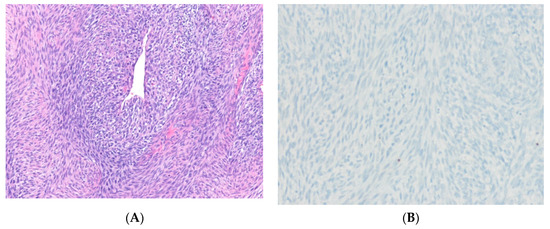

12.1. Malignant Peripheral Nerve Sheath Tumor